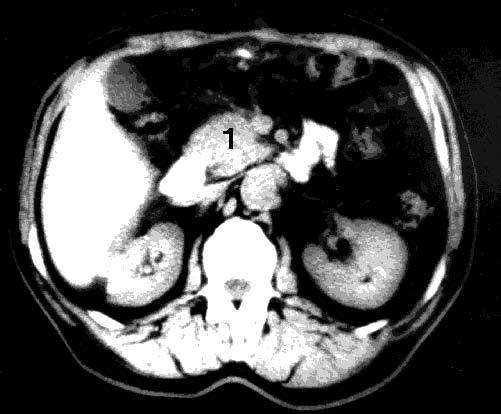

Существенное значение в диагностике опухолей ПЖ имеет компьютерная томография (КТ). Основными признаками КТ, позволяющими заподозрить РПЖ, являются увеличение размеров железы на локальном участке, бугристые контуры ПЖ в этой области, наличие опухолеподобного гиподенсного узла, опухолевая инвазия перипанкреатической клетчатки. Расширение ГПП при КТ диагностируется гораздо реже, чем при УЗИ, что связано с большой толщиной срезов при КТ (5–8 мм). Диагностическая точность КТ составляет 72–91 %. Разрешающая способность КТ близка к таковой при УЗИ, хотя метод обладает несколько большей информативностью в установлении распространения РПЖ на окружающие органы и структуры, в выявлении регионарных метастазов (рис. 99).

Рис. 99. Компьютерная томография. Рак головки ПЖ. На снимке видна гиподенсная бугристая опухоль головки ПЖ 4x5 см (1)